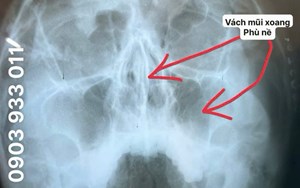

Địa chỉ : 50 Phan Huy Ích, Phường 15, Quận Tân Bình, TP. HCM.

CSKH: 0934 117 009

Tư vấn: 0903 933 011 (Ms.Điểu)/ 0934 117 009 (Mr. Nhung)

Hotline: 0903 933 011 - 028.3815.1615